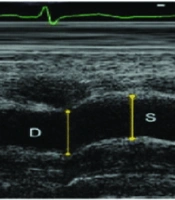

Comparing the Effect of Age and BMI on Aortic Elasticity in Diabetes Mellitus Type I and Healthy Children

Noor Mohammad Noori

,

Alireza Teimouri

*

Shima Gurui Sardo

|

Final Published